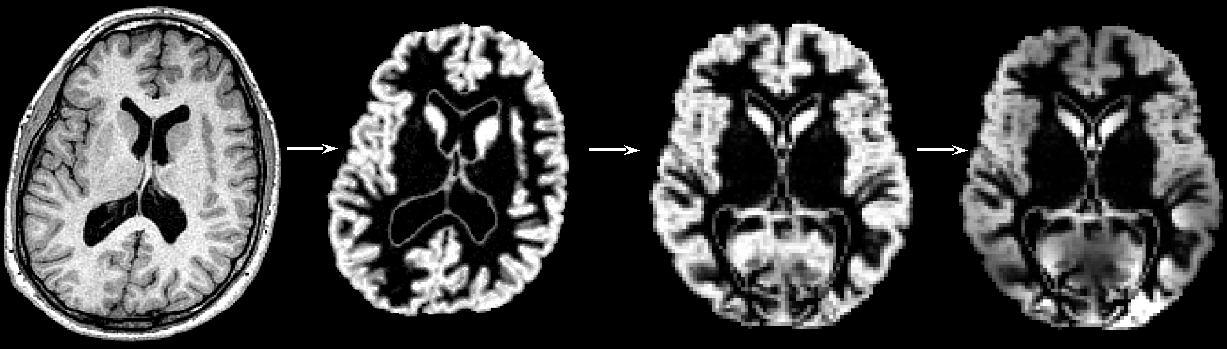

"Structural data was analysed with FSL-VBM (Douaud et al., 2007, http://fsl.fmrib.ox.ac.uk/fsl/fslwiki/FSLVBM), an optimised VBM protocol (Good et al., 2001) carried out with FSL tools (Smith et al., 2004). First, structural images were brain-extracted and grey matter-segmented before being registered to the MNI 152 standard space using non-linear registration (Andersson et al., 2007). The resulting images were averaged and flipped along the x-axis to create a left-right symmetric, study-specific grey matter template. Second, all native grey matter images were non-linearly registered to this study-specific template and "modulated" to correct for local expansion (or contraction) due to the non-linear component of the spatial transformation. The modulated grey matter images were then smoothed with an isotropic Gaussian kernel with a sigma of ?? mm. Finally, voxelwise GLM was applied using permutation-based non-parametric testing, correcting for multiple comparisons across space."

First, all brain-extracted images are segmented into GM, WM and CSF. Then, GM images selected in the template_list file (*_struc_GM) are affine-registered to the GM ICBM-152 template, concatenated and averaged. This averaged image is then flipped along the x-axis and the two mirror images then re-averaged to obtain a first-pass, study-specific "affine" GM template ("template_GM_init"). Second, the template_list GM images are re-registered to this "affine" GM template using non-linear registration, concatenated into a 4D image called "template_4D_GM", averaged, flipped along the x-axis. Both mirror images are then averaged to create the final symmetric, study-specific "non-linear" GM template at 2x2x2mm3 resolution in standard space.

The final script will non-linearly register all your GM images to the study-specific template and concatenate them into a 4D image (GM_merg) in the stats directory in your working FSL-VBM directory. The FSL-VBM protocol also introduces a compensation (or "modulation") for the contraction/enlargement due to the non-linear component of the transformation: each voxel of each registered grey matter image is multiplied by the Jacobian of the warp field (see Good et al., 2001). All the modulated registered GM images are concatenated into a 4D image in the stats directory (GM_mod_merg) and then smoothed (GM_mod_merg_s3 for instance) by a range of Gaussian kernels; sigma = 2, 3, 4mm, i.e., approximately from FWHM = 2x2.3 = 4.6mm to FWHM = 9mm.